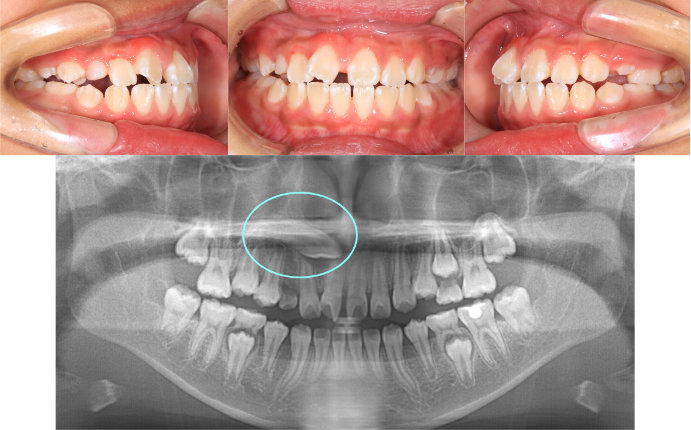

| Case1 |

| 出っ歯 |

| <治療前> |

| <治療後> |

| 主訴 |

前歯が出ている |

| 診断名 |

上顎前突 |

| 年齢 |

8歳 |

| 使用装置 |

マルチブラケット装置 |

| 抜歯部位 |

永久歯の抜歯は無し |

| 治療期間 |

2年4か月 |

| 治療費概算 |

検査・診断料:5万円+税 装置・技術料:25万円+税 おおよそ1か月ごとの処置・管理料:5,000円+税 保定装置料:5万円+税 |

| リスク・副作用 |

う蝕 歯根吸収 |